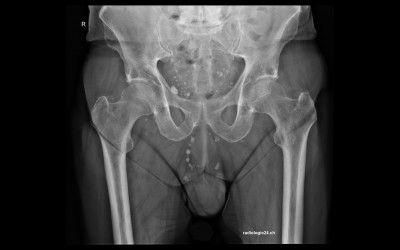

Röntgenfall des Monats August 2017 mit Auflösung

75 jähriger Patient therapierefraktäre Becken-/Hüftschmerzen rechts Diagnose/weitere radiologische Diagnostik?